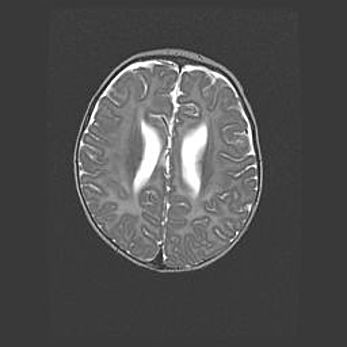

Множественные мелкие кисты перивентрикулярной области.

Киста прозрачной перегородки.

Возраст: 28 дней

Вес: 2400 г

Пол: женский

Окружность головы: 33 см

Срок гестации: 34 недели

Перивентрикулярная киста – это полостное образование в околожелудочковых областях белового вещества головного мозга. С морфологической точки зрения – это мелкоочаговая зона коагуляционного некроза, возникшая после инфаркта белого вещества. Наиболее часто поражаются начальные отделы задних рогов боковых желудочков. Обычно образования заполнены жидкостным содержимым.

Киста прозрачной перегородки может располагаться в переднем отделе межжелудочковой перегородки, в области мозолистого тела и мозжечка.